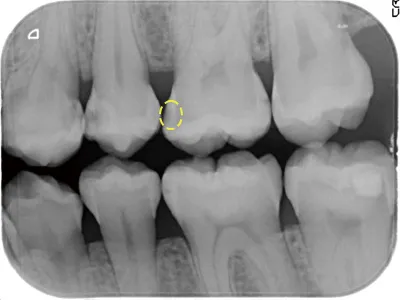

レントゲンに写った虫歯の進行が停止

写真5 2023年5月撮影

写真4から写真5は、なんと10年以上もむし歯が進行していません。たとえむし歯が象牙質に進行(歯に穴が空いている)していても、非修復治療で、進行を止めることができるのです。